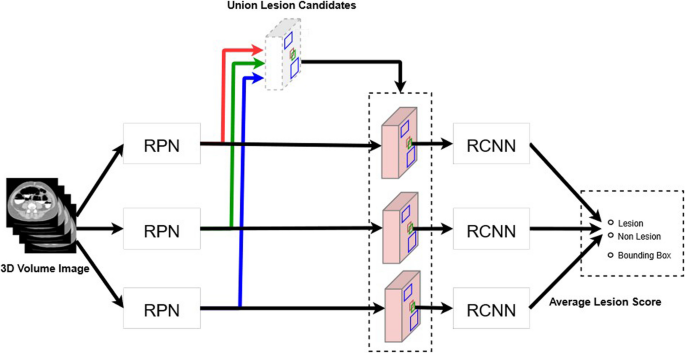

Ensemble estimation

The aforementioned network was trained during this study using two groups of datasets with different characteristics as learning datasets. The data from the previous two trials primarily consisted of small lesions. In contrast, the Saitama and Tonan datasets included only large lesions as learning targets, excluding small lesions. When the algorithm, trained on both large and small lesions together, was tested on the Saitama and Tonan datasets, there was a possibility that its performance in detecting small lesion would decrease. We avoided this problem by training the neural network using the following two patterns: the pattern that included the Saitama and Tonan datasets as training data and the pattern that did not include these datasets. Furthermore, the neural network trained on the data of the two previous trials was prepared using the same data. We integrated the outputs of these three different neural networks with the inference (Fig. 4).

Schema of the process of integrating the outputs of three different neural networks. The first is a neural network trained on data from two previous trials with many small lesions and data from Saitama and Tonan with mainly large lesions. The second is a neural network trained on data from Saitama and Tonan. The third is a neural network trained on data from two previous trials. A trained model will have slightly different characteristics even with the same training data and same neural network; therefore, it is known that accuracy can be improved by using many trained models to obtain the final result by majority vote, which is called AI ensemble learning. RCNN: region-based convolutional neural network; RPN: region proposal network.

The detection algorithm outputs the lesion probability for the lesion candidate as a score. If this score is above a preset threshold, then the candidate lesion will be detected by AI and the sensitivity will be calculated. The neural network adopted for the present study was composed of two subnetworks: candidate lesion detection (during the first stage), which adopted all the candidates that were output by the three network types to detect candidate lesions of all sizes, and the simple average of these values, which were taken from the three networks to obtain the final lesion probability score (during the second stage). During the present study, the threshold value from 0 to 1 was divided into increments of 0.01 to evaluate the performance of CAD, which is a preliminary step of an image interpretation test, and the number of FP lesions detected was determined. For sensitivity, free-response receiver operating characteristic (FROC) analysis was performed and FROC curves were obtained from the true positive fraction and the numbers of false positives per CT image.